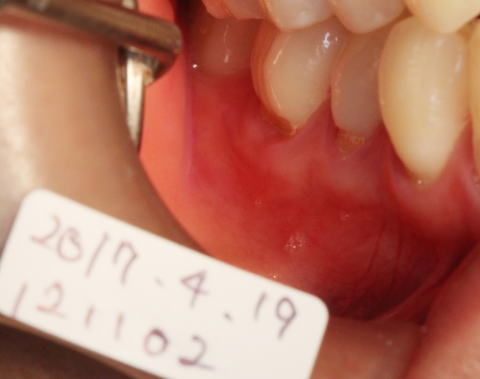

2017-07-22 剥離すると歯頚部が骨で覆われていないのがわかります。 |

2017-07-22 骨が足りない所に骨補填剤等を充填して歯肉弁歯冠側移動術を行いました。 |